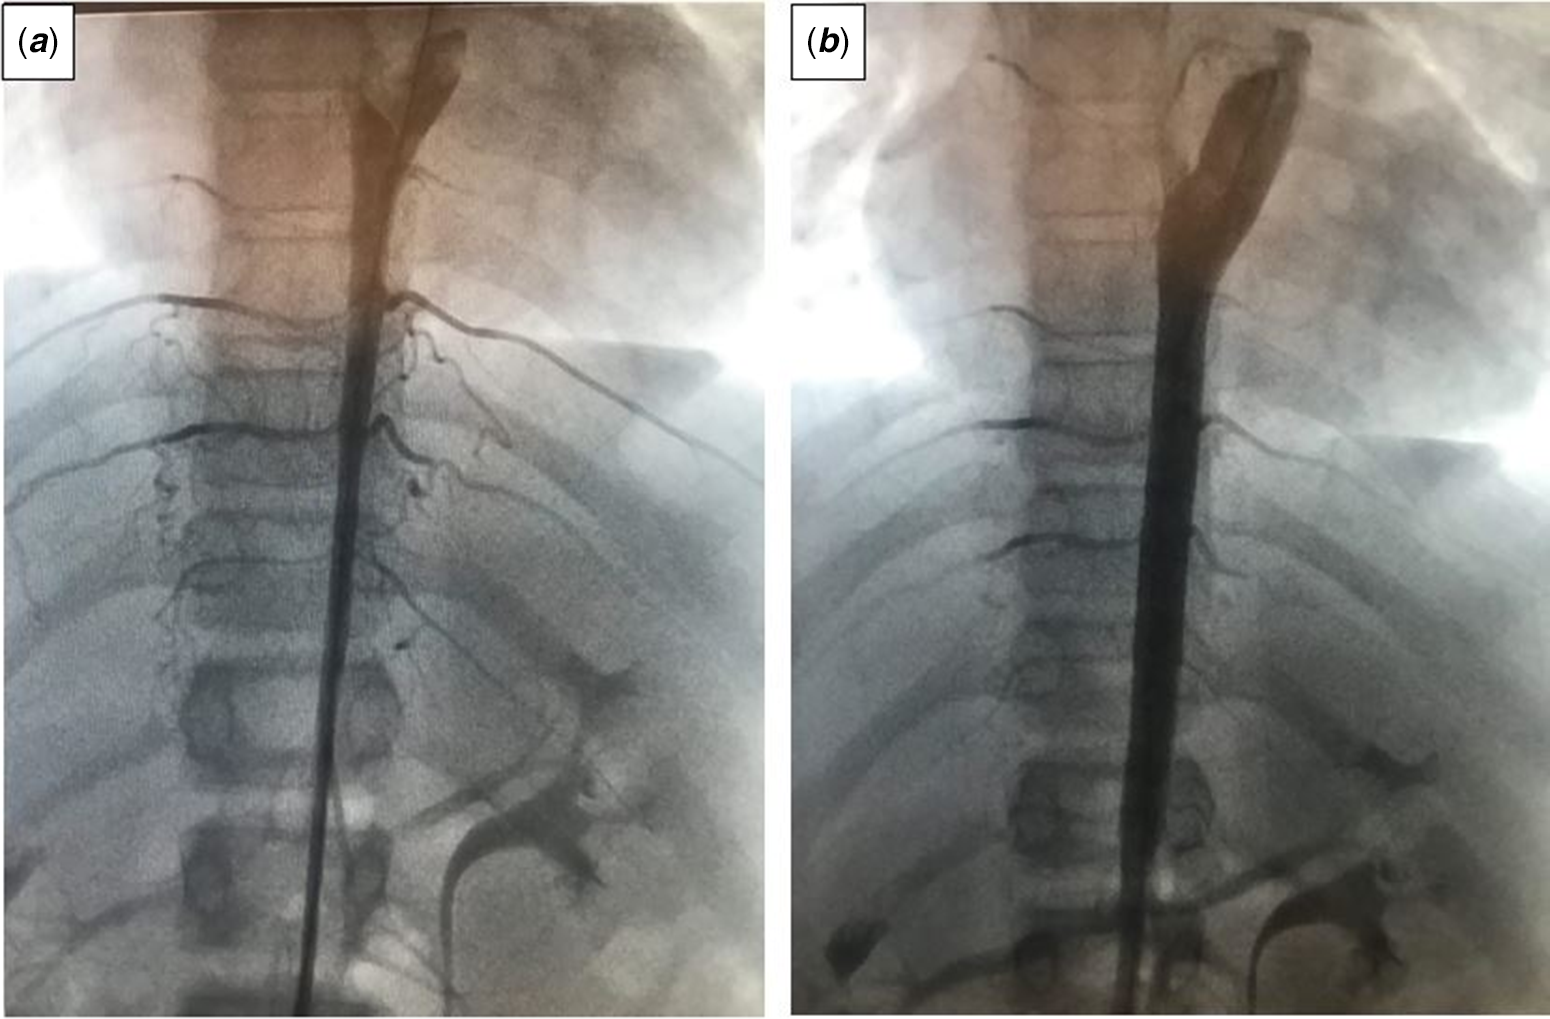

Cardiac catheterisation was performed under general anaesthesia. The angiographic study revealed that the descending aorta in the middle aortic segment was hypoplastic with a calibration of 5.5–6 mm (Fig 2a). Besides, hypoplasia was observed in the proximal part of the right renal artery. Before stent implantation, to safely advance the long sheath, a predilatation was performed using a 5 × 2 cm Tyshak II balloon. After then, a 40x9 mm Cook Formula stent was gradually inflated. Later, a 40 × 9 mm second Cook Formula stent was partially overlapped with the first and gradually inflated. As it was noticed that there was a pressure gradient in the distal part of the stents, a 7 × 58 mm stent was inflated gradually in overlap. Control angiography demonstrated good position of the stents with aortic final diameter of 9 mm, and maximum gradient of 15 mmHg remained between the ascending and descending aorta.

Figure 2. Catheter angiography images of the patient before ( a ) and after ( b ) stent implantation.